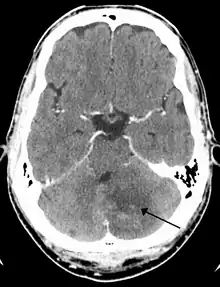

Cerebellar strokes account for only 2-3% of the 600,000 strokes that occur each year in the United States.[3] They are far less common than strokes which occur in the cerebral hemispheres. In recent years mortality rates have decreased due to advancements in health care which include earlier diagnosis through MRI and CT scanning.[4] Advancements have also been made which allow earlier management for common complications of cerebellar stroke such as brainstem compression and hydrocephalus.[4]